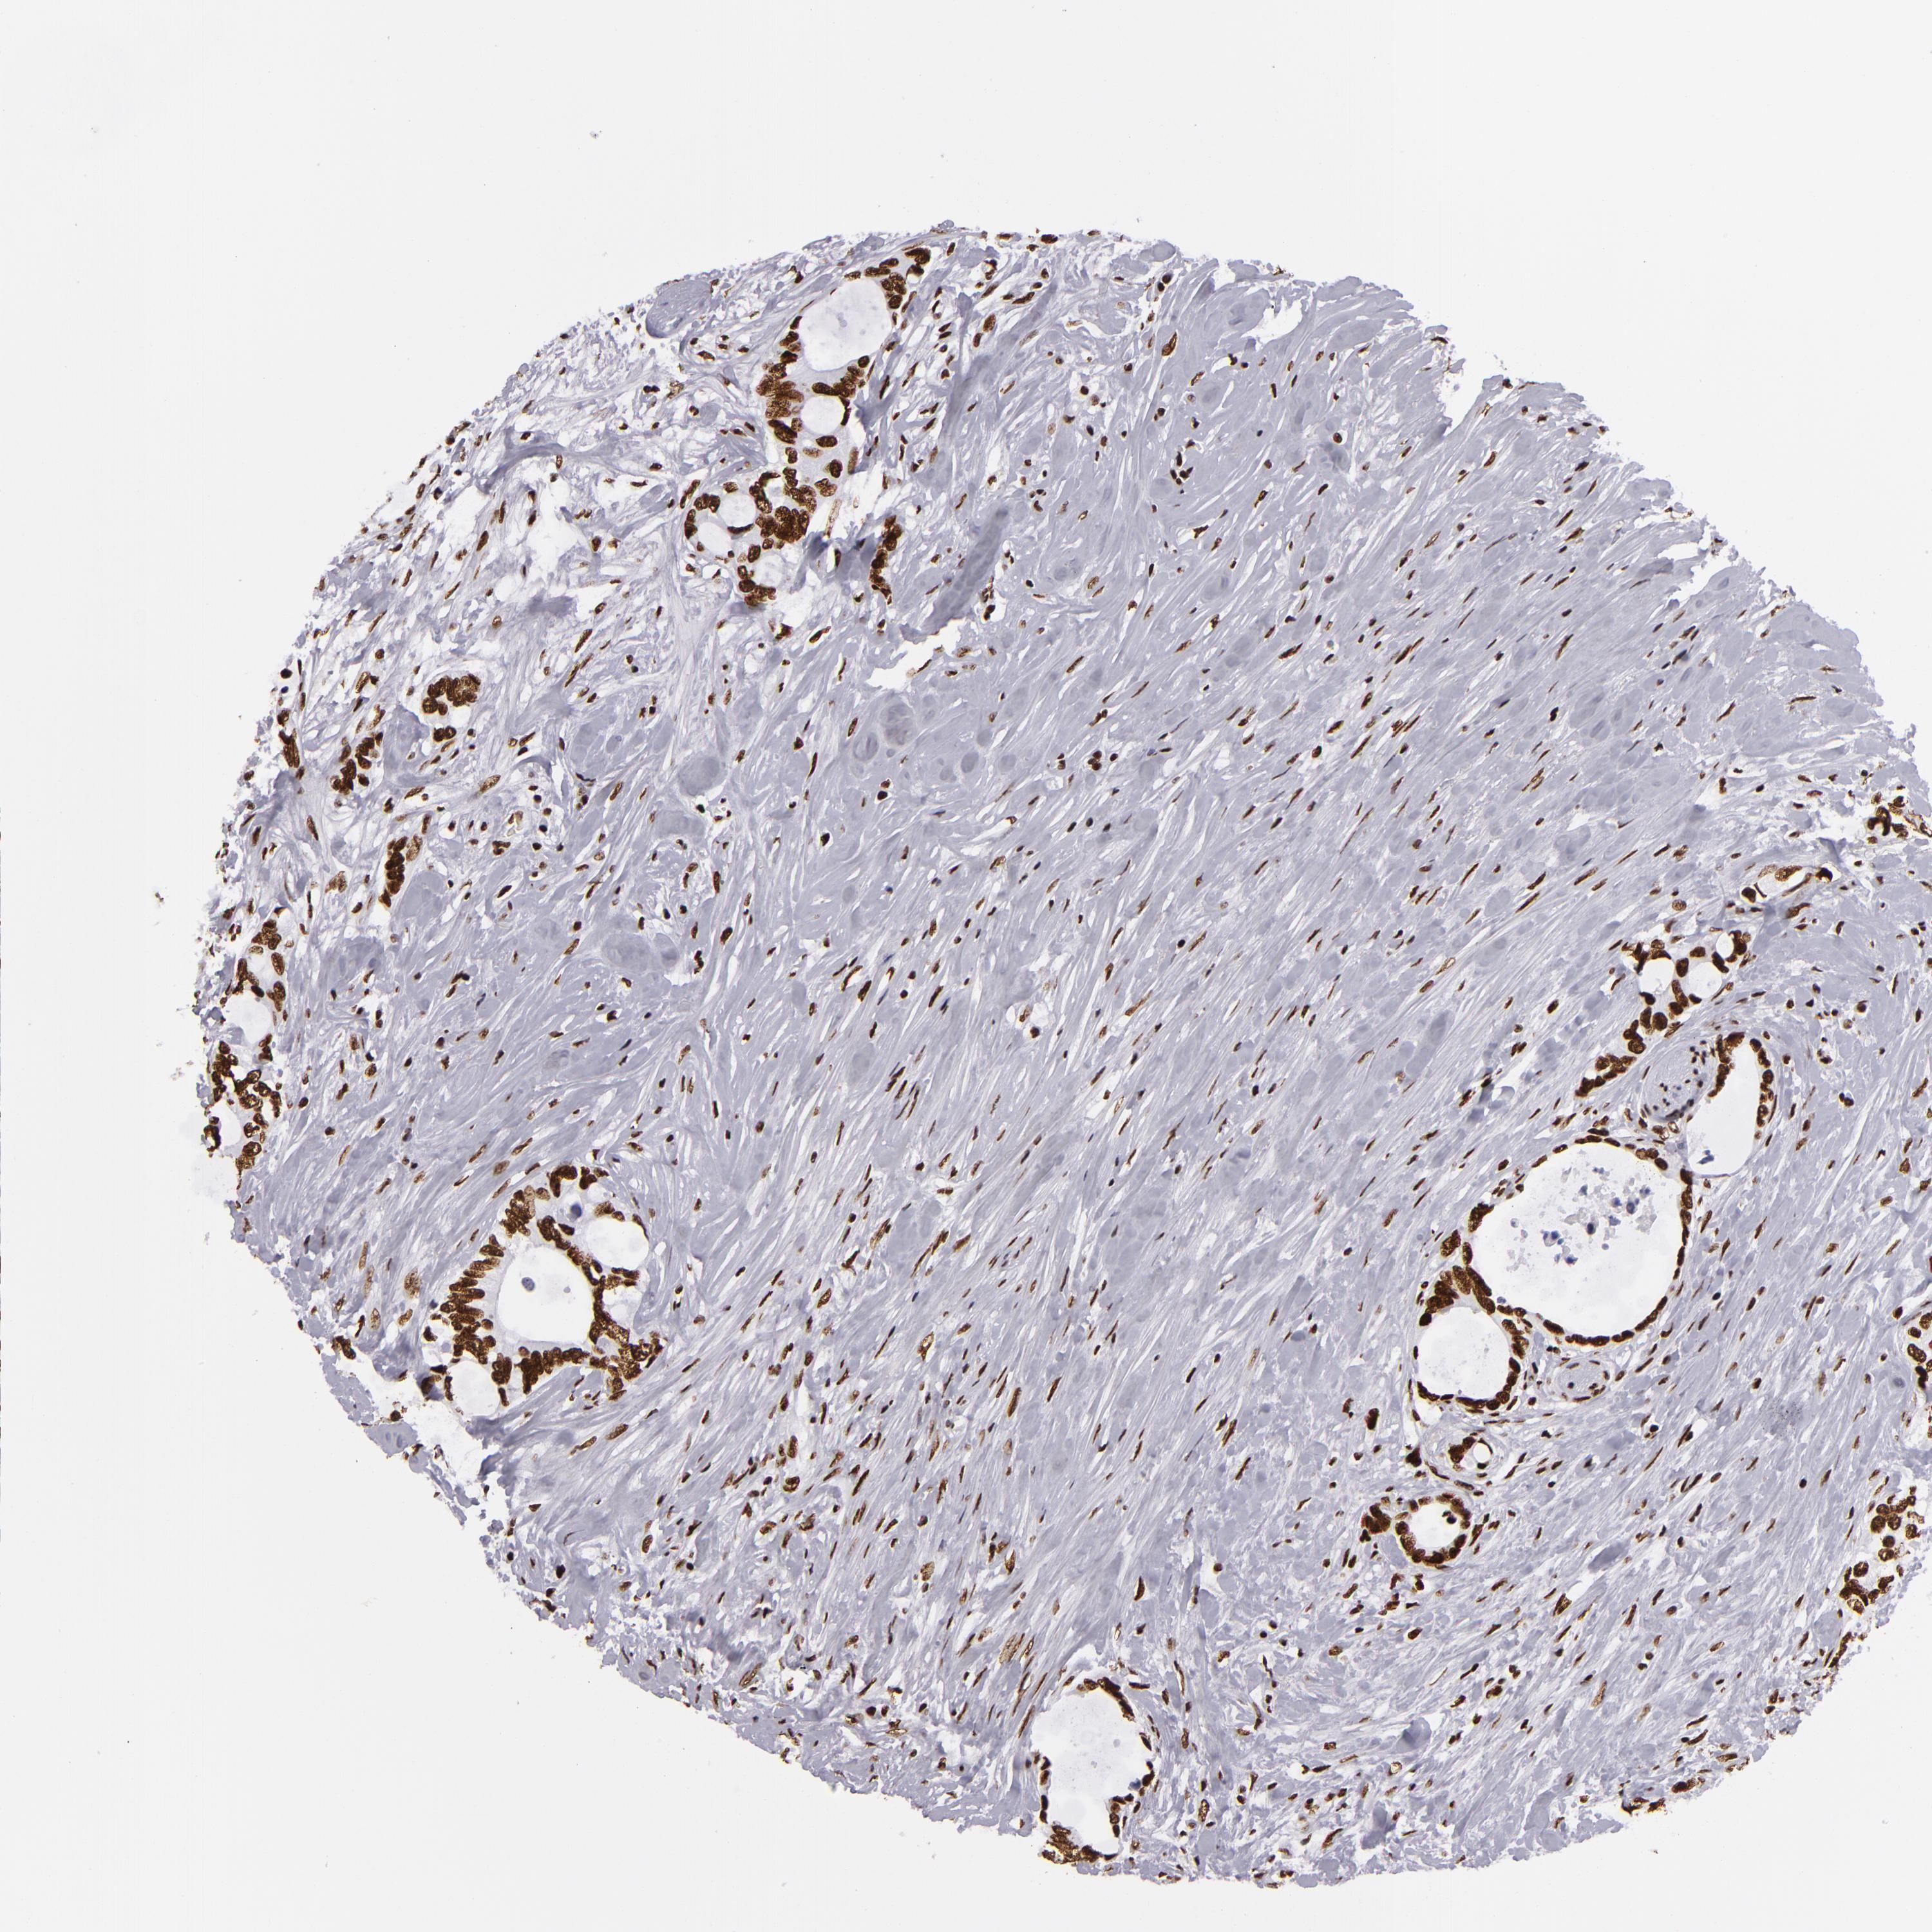

CANCER COLORECTAL CANCER Show tissue menu

Colorectal cancer

Human cancer